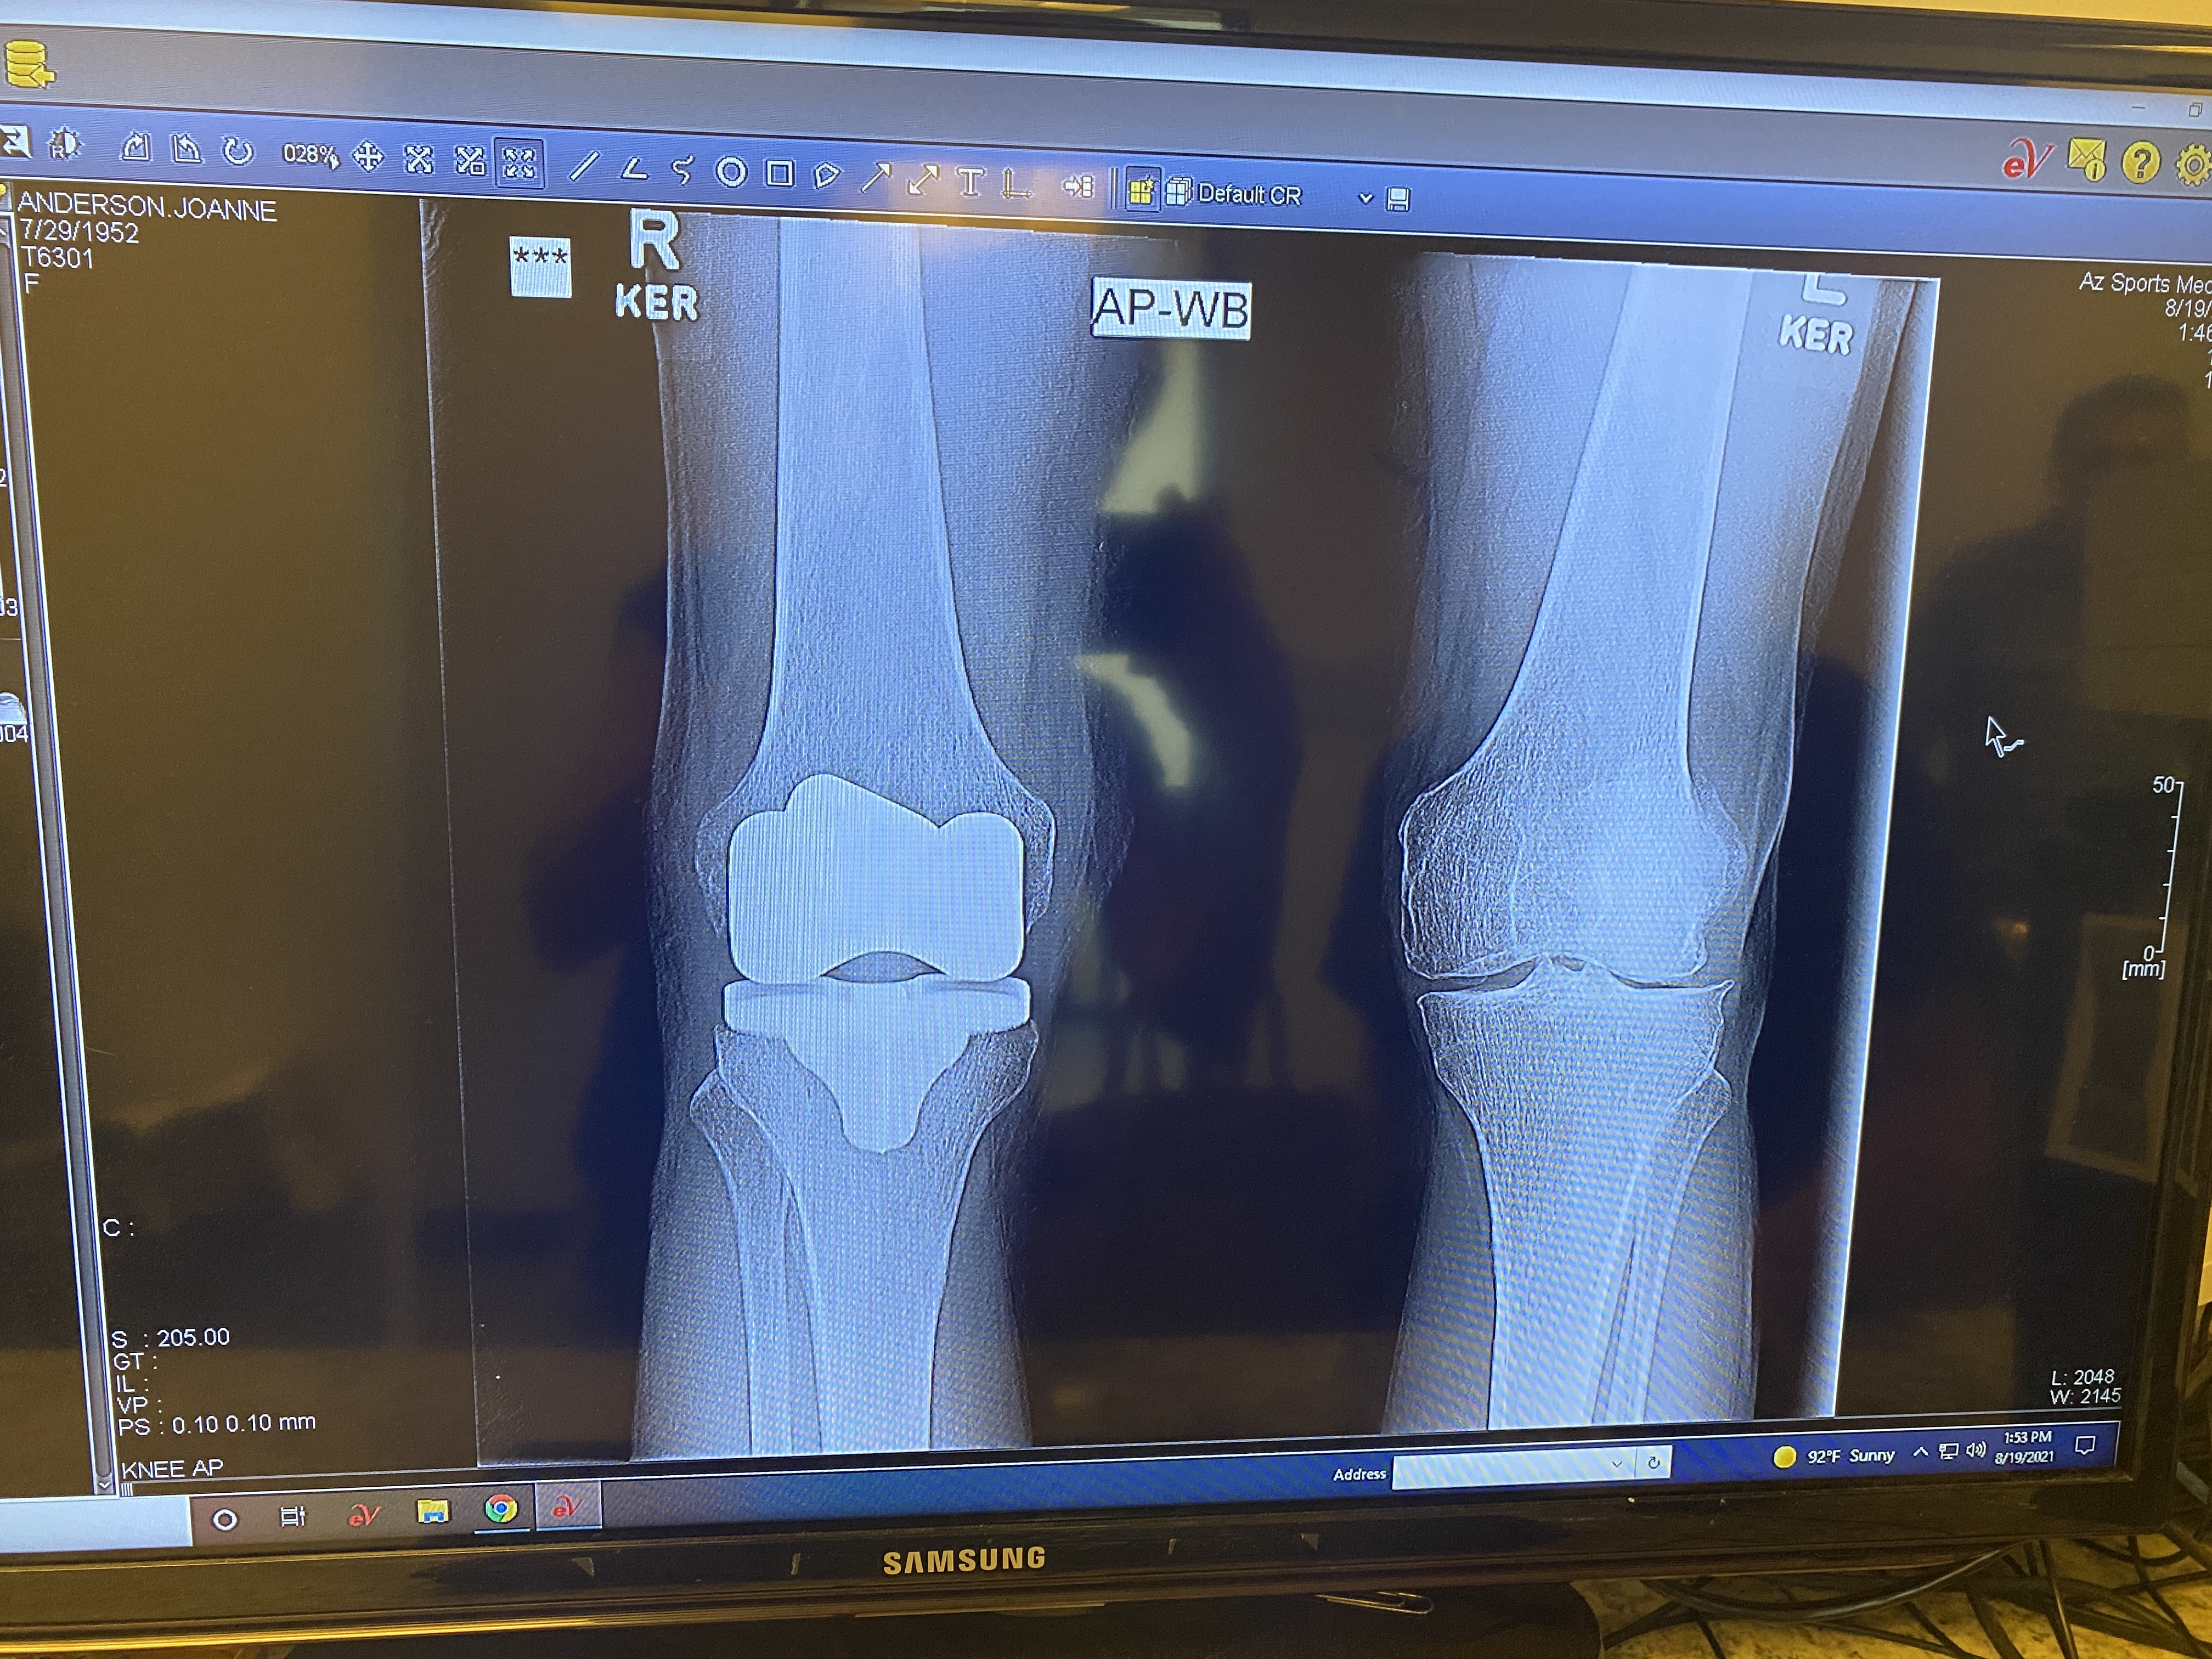

And of course, I had to have one more running photo of me and my sis. State #50 in the bag! We have dozens of these photos, but it doesn’t make any of them any less special, and this one more than most. I could never have completed this journey without her constant encouragement and support, cheering me on every step of the way, through broken bones, illness, arthritis and knee surgery. She is the ace in my deck and always has been. The fact that we are 70 and 66 doesn’t mean a thing to her. You just dig in and get ‘er done.